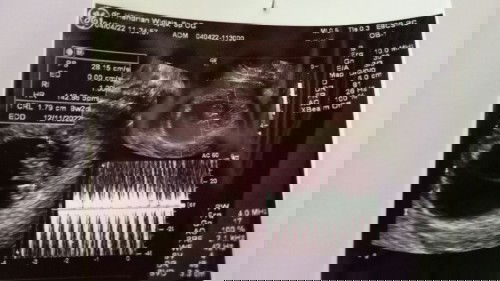

37week5day tapi blm prnh konpal, masih santuy santuy aja aku liat bumil lainnya udh banyak keluhan, sdgkn anakku msh asik ngereog tiap malem😄 padahal udh masuk panggul dr 34week, dan posisinya udh mapan bgt pernah sekali aja nyeri perut bawah itupun ga lama Hpl 12 november #firstmom #firstbaby